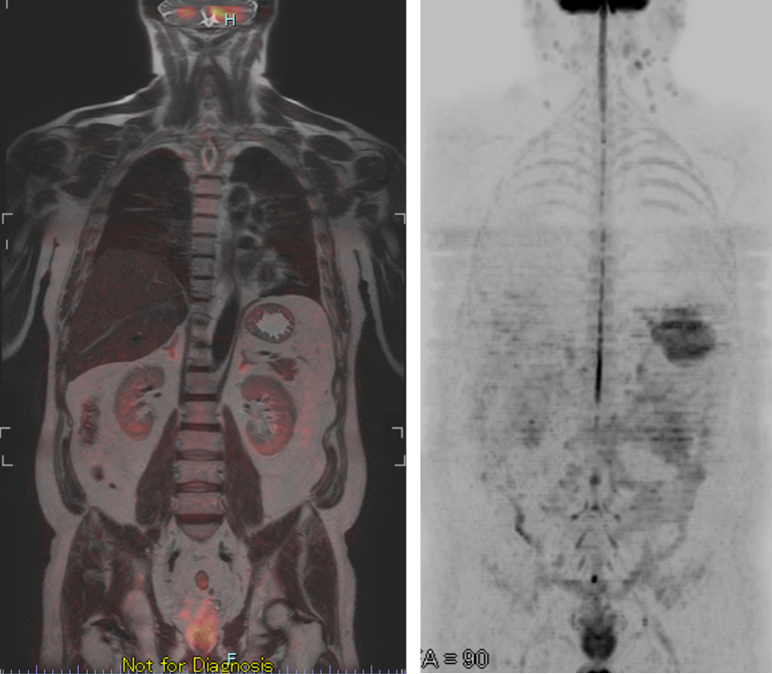

<ドゥイブス画像例>

全身MRI検査(ドゥイブス法)とは、全身のがんや炎症の有無を調べることができるスクリーニング検査です。

PET検査と比較して短時間で身体への負担が少ないためおすすめです。(頸部、乳房、肝臓、胆のう、腎臓、膵臓、前立腺(男性)、子宮・卵巣(女性))

また、大腸がん、膵臓がん、肝臓がん、特にPETーCTが不向きとされている腎がん、尿管がん、膀胱がん、前立腺がんのスクリーニング検査に向いています。